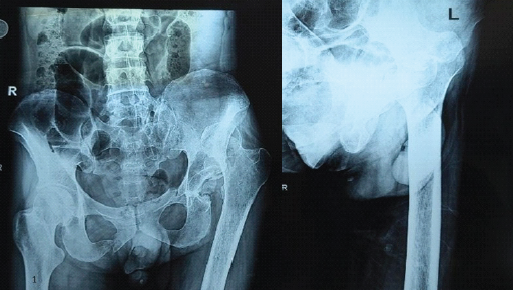

A 48-year-old male presented to us with 1½-year-old posterior hip dislocation (Fig. 1) following a road traffic accident.

Figure 1: Preoperative plain radiograph showing posterior dislocation of the left hip.